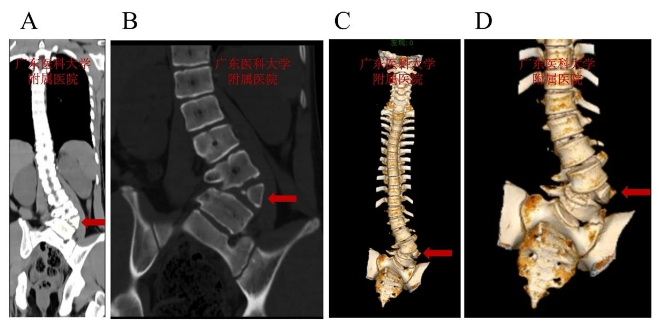

术前脊柱CT:L4呈楔形半椎体畸形,腰弯以L4半椎体为顶锥明显向左侧凸

术前脊柱CT:见L2左侧椎弓根缺如